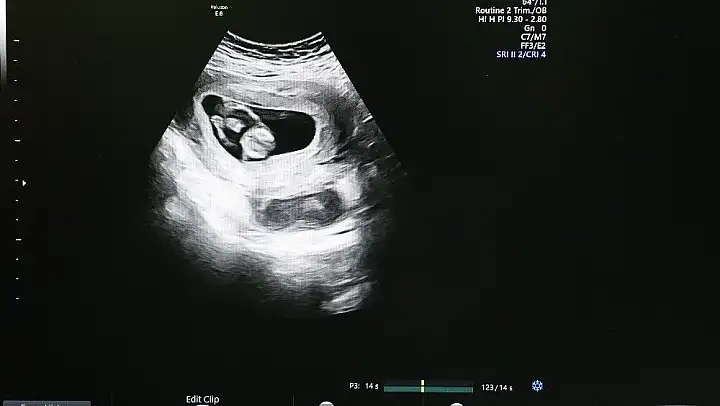

Sivas Cumhuriyet Üniversitesi Araştırma ve Uygulama Hastanesi, Kadın Hastalıkları ve Doğum Kliniği'nde yaklaşık 1 yıl önce hizmet vermeye başlayan 'Ultrasonografi Cihazı' sayesinde anne karnındaki bebeğin bütün yapısal problemleri tespit edilebiliyor.

Cihaz sayesinde anne karnındaki bebeklerde zor ve güç olan problemleri kolaylıkla görüntüleyebildiklerini anlatan Doç. Dr. Çağlar Yıldız, 'Bebeğin vücut yapısında bulunan tüm problemleri tespit edebiliyoruz. Örneğin; kalp, beyin gelişimiyle ilgili problemleri, kol ve bacak, yüz deformiteleriyle ilgili problemleri rahatlıkla ortaya koyabilmekteyiz' şeklinde konuştu.